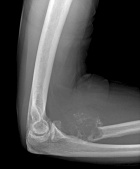

68 year old male with right elbow pain

Zoom image: Radiological image Radiological image.